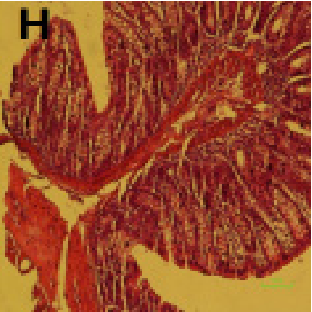

Figure 9

Protective and Therapeutic Effects of Aloe Vera Gel on Ulcerative Colitis Induced …